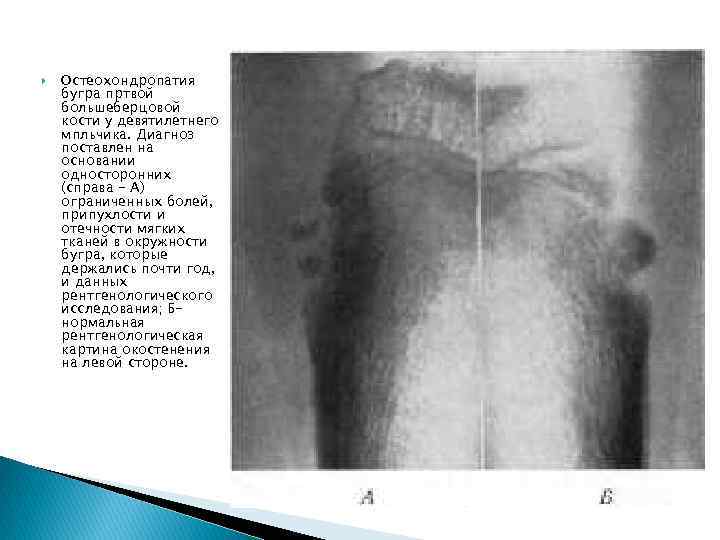

Остеохондропатия бугра пртвой большеберцовой кости у девятилетнего мпльчика. Диагноз поставлен на основании односторонних (справа - А) ограниченных болей, припухлости и отечности мягких тканей в окружности бугра, которые держались почти год, и данных рентгенологического исследования; Бнормальная рентгенологическая картина окостенения на левой стороне.